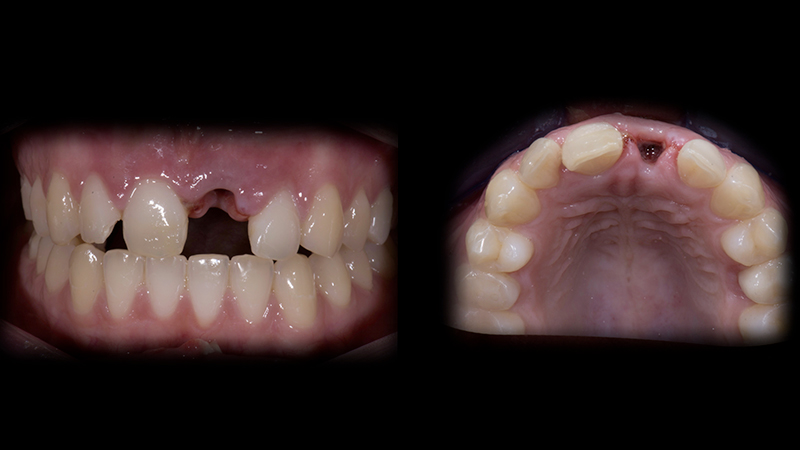

Per un trauma frontale, una paziente di 24 anni con sorriso gengivale, perde il dente 2.1. Il dente 1.1 è dislocato palatalmente e il dente 1.2 presenta un danno al margine incisale (Fig. 2a, Fig. 2b). La CBCT mostra una frattura in entrambe le placche vestibolari ossee, in corrispondenza dei due incisivi centrali superiori (Fig. 3).

Stato iniziale

Fig. 2a - Stato iniziale.

Stato iniziale intraorale

Fig. 2b - Stato iniziale intraorale.